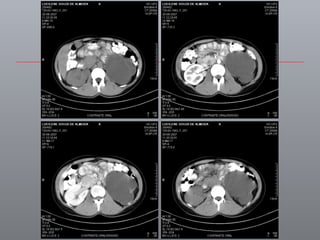

PRÉ-OPERATÓRIO ABORDAGEM DEPENDE DE Hand-assisted Transabdominal Retroperitoneal Sua experiência Patologia Anatomia

AVANÇOS DE IMAGENS / ONCOLOGIA PESQUISANDO O TUMOR Limites estratégicos / precisão cirúrgica IRCAD